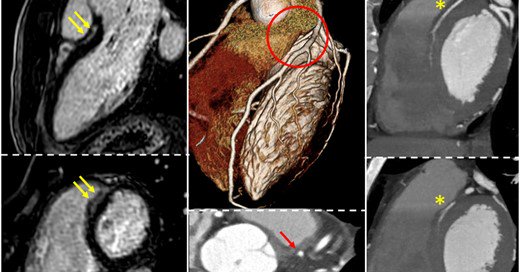

📌Evolving Diagnostic Criteria for Arrhythmogenic Cardiomyopathy #CardioEd #CardioTwitter #ePeeps @JAHA_AHA

2

72

167

Just published on the @JAHA_AHA: from the original 1994 ITF criteria to the Padua criteria for the diagnosis of arrhythmogenic cardiomyopathy. #arvd #arvc #cmr #cardiomyopathy #Cardiology

@DCorradoCardio @Cipeciop1964 @albcipri6

0

3

9